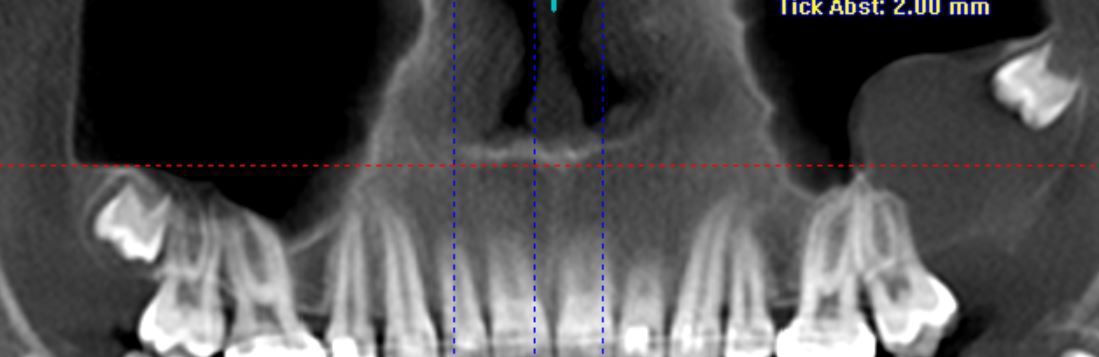

Digitale Volumentomographie

Die digitale Volumentomographie ist ein präzises röntgenologisches 3-D Verfahren zur Darstellung knöcherner Strukturen des gesamten Kopfbereiches. Je nach Fragestellung können auch kleinere Ausschnittsdarstellungen vorgenommen werden. Die Technik gleicht einer konventionellen Übersichtsaufnahme, wobei hier jedoch der Mund geschlossen bleiben kann. Die generierten Aufnahmen gleichen denen eines konventionellen CT, jedoch bedingt die Aufnahmetechnik für zahnärztliche Fragestellungen eine Reihe Vorteile:

- Wahlweise höhere Auflösung

- Geringere Strahlenbelastung

- Weniger Metallartefakte ( Aufnahmequalität mindernde Störungen) durch Zahnfüllungen und prothetische Rekonstruktionen

Ihr Zahnarzt oder Arzt überweist Sie häufig mit einer speziellen Fragestellung wie

- Klärung des Knochenangebots vor einer Implantatversorgung

- Verlauf des Unterkiefernerven vor Weisheitszahnentfernungen

- Lage und Prognose retinierter Zähne (Kieferorthopädie)

- Frakturausschluss

- Zystenausdehnung

- unklare Schwellungen-, Schmerzen

- anatomische Situation der Nasennebenhöhlen (ORL)

Zuweiser: Patienten können direkt über die Homepage zur digitalen Volumentomographie angemeldet werden.